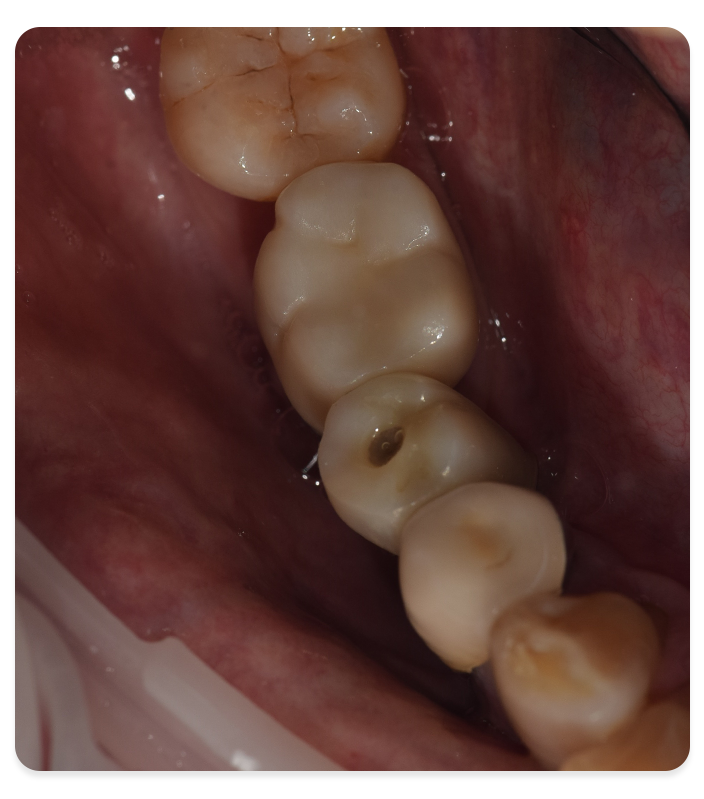

3D 진단을 바탕으로 개인별 뼈 · 잇몸 · 교합 상태를

평가하여 가장 적합한 임플란트 계획을 수립합니다.

CBCT 기반 플래닝과 서지컬 가이드를 통해 안정성을 지향하며, 회복부터 위생 관리, 정기 점검까지 일관된 관리를 제공합니다.

3D 진단을 바탕으로 개인별 뼈 · 잇몸 · 교합 상태를 평가하여 가장 적합한 임플란트 계획을 수립합니다.